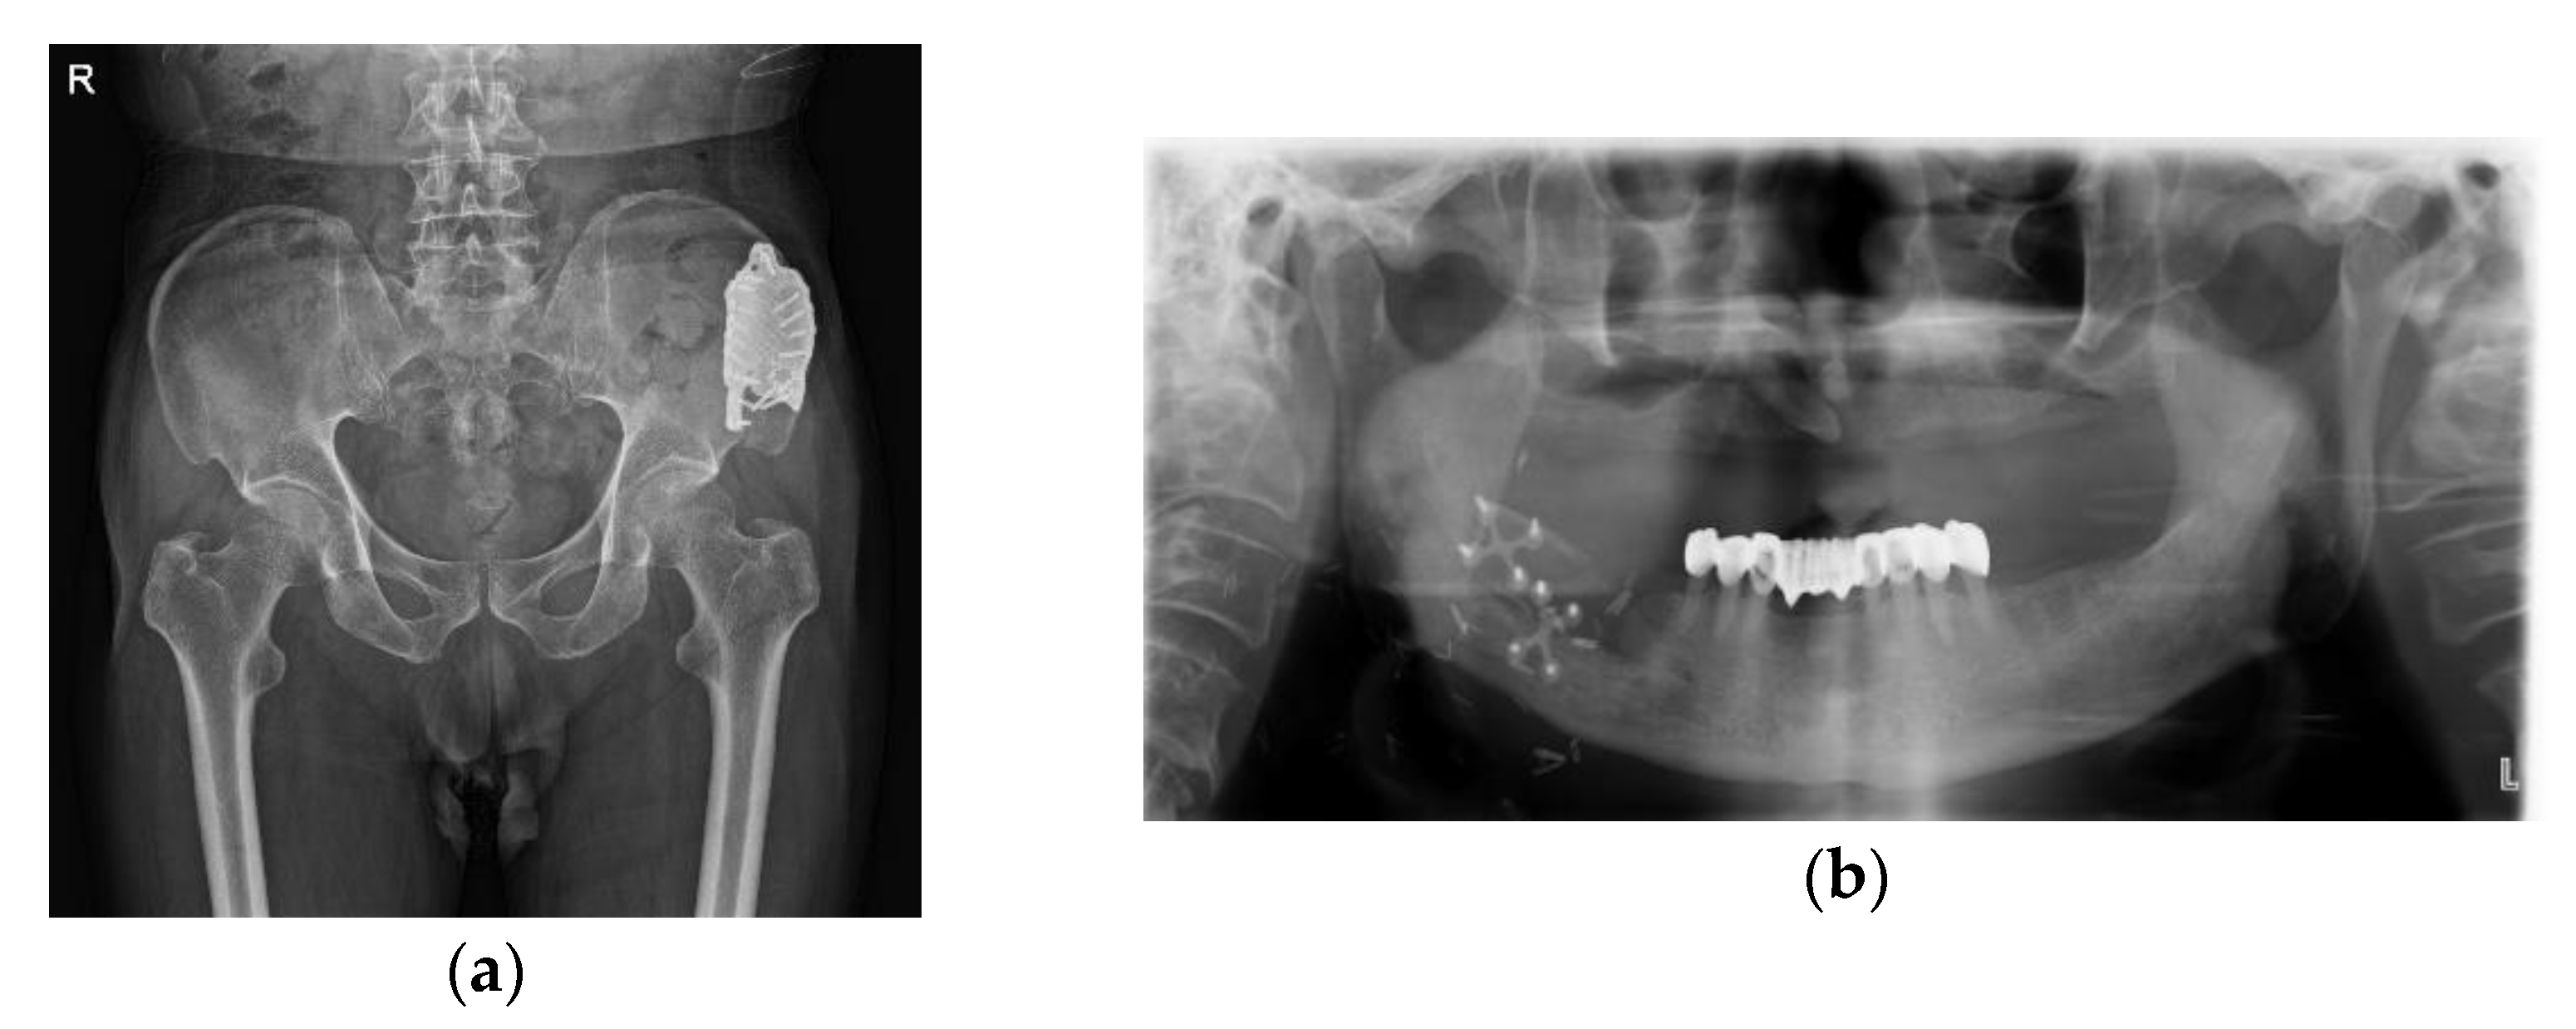

2.1.2. Surgical Technique

2.2. Case 2: Ameloblastoma on Left Mandibular Body and Angle

2.2.2. Surgical Technique